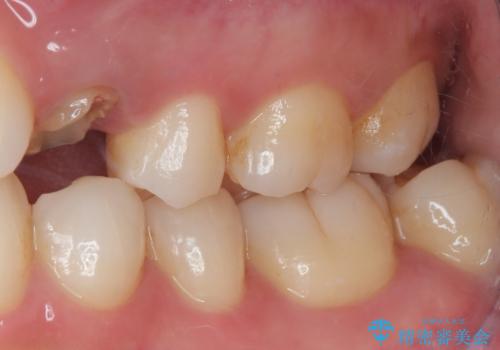

左上小臼歯を抜歯し、矯正治療でスペースを閉じる方法と左上小臼歯を抜歯し、抜歯即時インプラントを行う方法、保存療法を行う方法の治療期間、費用、メリット・デメリットについて説明したうえで治療期間をできるだけ短くしたいという希望があったため抜歯即時インプラント治療を選択されました。

矯正・インプラント・保存治療を含めた総合的な診断によって、患者様に合った選択肢が見つかることがあります。